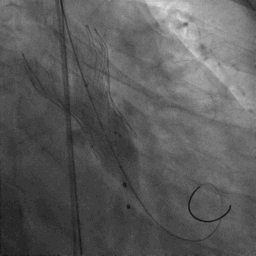

手术过程:

患者麻醉方式采取监护麻醉,建立静脉通路后,穿刺右肱动脉置入鞘管,穿刺右股动脉预置Proglide缝合器,置入动脉鞘管。右股静脉宜置入鞘管,经股静脉置入临时起搏器。经右股动脉行冠脉造影提示冠脉多处50%-60%狭窄。塑性后的加硬导丝送至左心室内,18mm球囊预扩张,主动脉根部造影提示右冠未见显影,右冠植入Chimney支架,同时释放TaurusElite® AV23主动脉瓣膜,造影示右冠血流通畅,瓣膜形态良好,结果满意。应用ProGlide缝合右股动脉穿刺部位并拔除临时起搏电极。术后患者即刻苏醒,安全返回普通病房。

主动脉根部造影

18mm球囊预扩张

23mm瓣膜精准定位

瓣膜+Chimney支架释放

瓣膜形态良好,结果满意